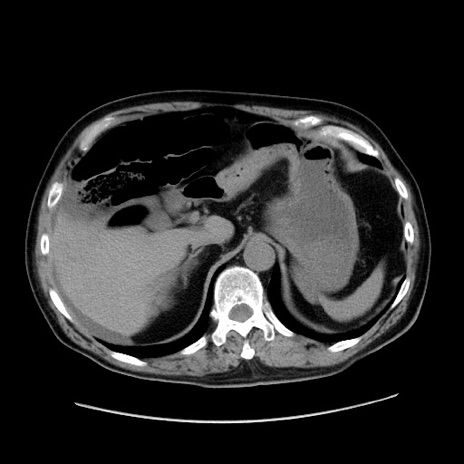

冠状断像

【症例】80歳代男性

【主訴】臍周囲痛

【現病歴】約6時間前から臍下部痛が出現。次第に腹部膨隆・背部痛も生じてきたため来院。背部痛の場所は変化しない。

【身体所見】意識清明、BT 36.3℃、BP  131/87mmHg、P 87bpm、SpO2 100%(RA)、臍周囲自発痛・圧痛あり、反跳痛なし、自発痛部位に一致して板状硬あり、腹部膨隆、腸雑音減弱、CVA tenderness両側陰性。

【データ】WBC 19600、CRP 0.33